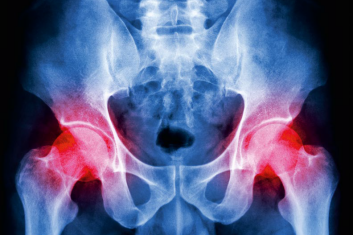

Natomiast Temat Numeru grudniowego wydania O Czym Lekarze Ci Nie Powiedzą poświęciliśmy chorobom stawu biodrowego. Zgodnie z danymi NFZ, co roku w Polsce odbywa się 54 490 endoprotezoplastyk pierwotnych tej struktury i aż 4 816 endoprotezoplastyk rewizyjnych. Tymczasem dzięki zawczasu podjętej profilaktyce części z nich można by uniknąć.

Boli mnie noga w biodrze...

Nie mogę chodzić dobrze... Zawadiaka w tej ludowej piosence wierzy, że obwiązanie nogi chustką to cudowne lekarstwo i zaraz ochoczo wskoczy na...

Krzywizny w konflflikcie

Strzykanie w biodrze to nie tylko udręka starszego pokolenia. Bywa, że na problemy z tym stawem narzekają całkiem młodzi ludzie, a nawet dzieci....